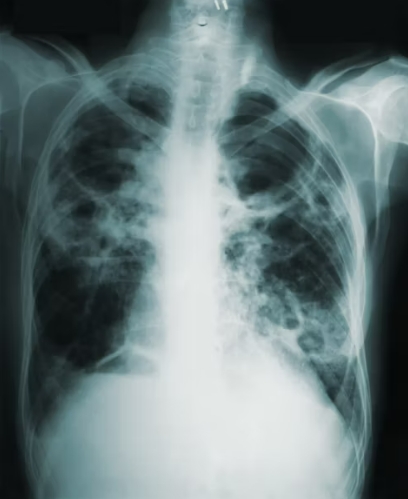

형태학적으로 폐결절은 고형 결절, 부분 고형 결절, 간유리 음영 결절로 구분됩니다.

고형 결절은 CT 상 선명하게 보이는 덩어리 형태이며, 간유리 음영 결절은 뿌옇게 흐린 형태로 관찰됩니다. 두 가지가 혼합된 형태는 부분 고형 결절이라 부릅니다. 이 구분은 추후 진단과 치료 방향을 결정하는 데 중요한 기준이 됩니다.